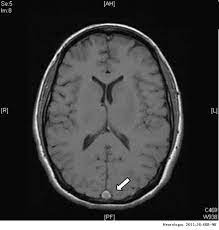

Primer informe de trombosis venosa cerebral después de la vacunación covid con virus inactivado (Sinopharm y Sinovac)

28 enero 2022